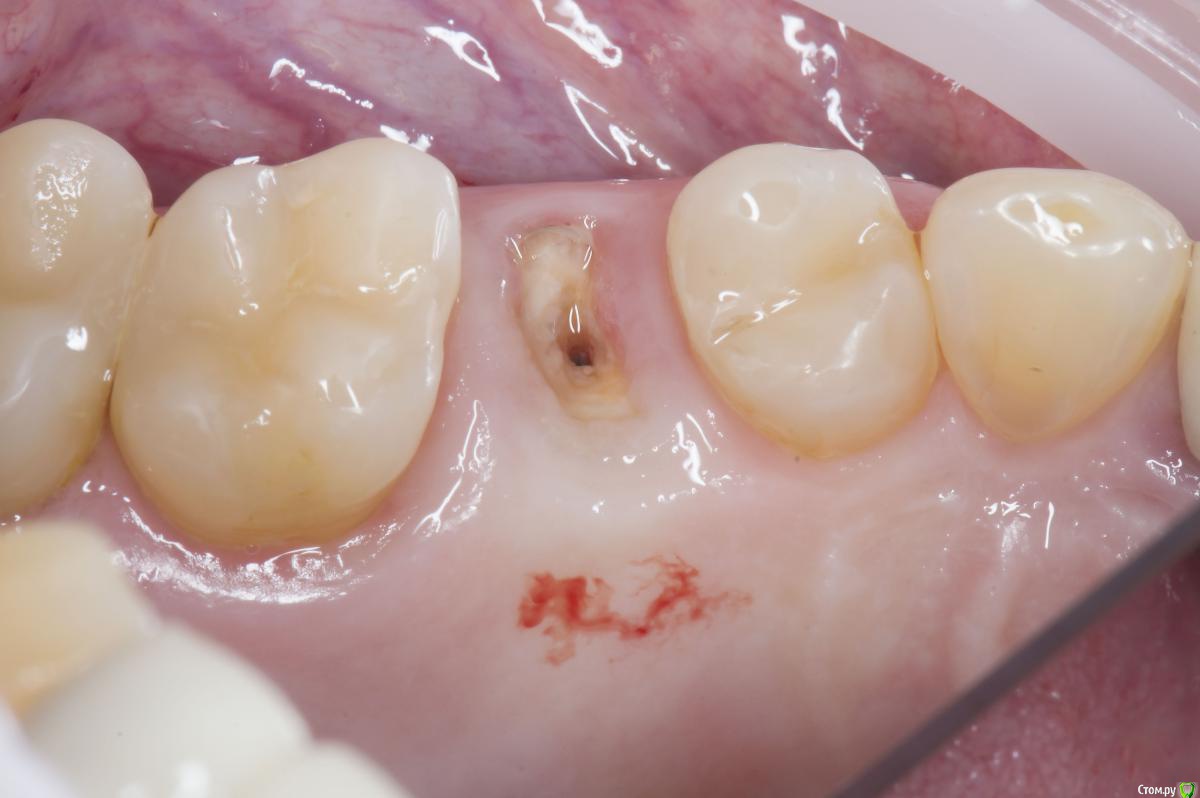

Sampson Опубликовано 10 августа, 2018 Поделиться Опубликовано 10 августа, 2018 (изменено) Очень мило для первого раза.. Здравствуйте коллеги.Сегодня поставил первый свой одномоментныйИзначальная картинаУдалениеСверление и контрольГрафтБолтКТФдмP.S. еще сдт взял с неба и вестибулярно подшил. А с неба заложил prf. Изменено 10 августа, 2018 пользователем Sampson 7 Ссылка на комментарий